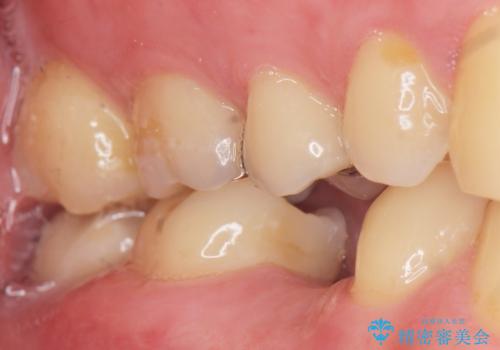

予算を抑えてしっかりとしたインプラント治療 30代男性

- 奥歯(右下5)のインプラントをご希望し来院された患者様です。

なるべく低予算でとのご希望により、アルファタイトインプラント(保証期間:3年)による治療を行いました。

自然な仕上がりと咬み心地に喜んで下さいました。

「低予算でしっかりした治療を受けることができた」とご満足頂けました。

インプラントの種類:アルファタイト

クラウンの種類:オールセラミッククラウン スタンダード